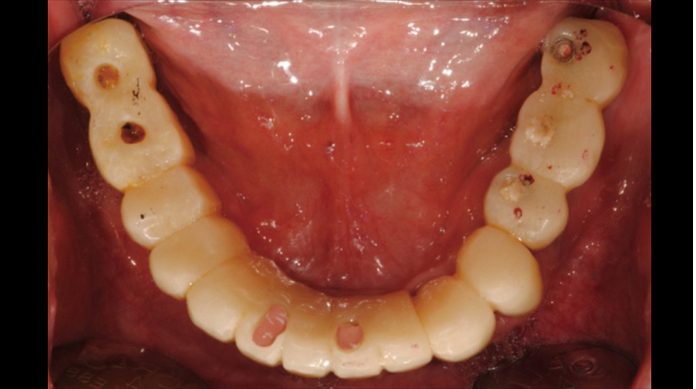

Clinical case: Full-mouth implants for mandibular & maxilla - restored using mixed prostheses

- Courtesy of Dr. Hyun Jun Kim, Korea -

Keywords

AnyRidge, full-mouth implants, mandibular, maxilla, edentulous, full mouth rehabilitation, Octa abutment, long-term clinical case, biological stability, Dr. Hyung Jun Kim

Products:

AnyRidge implant system